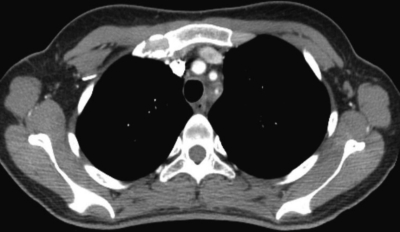

血液所見:赤血球 403 万、Hb 10.0 g/dL、Ht 30 %、白血球 10,900 (桿状核好中球 28 %、分葉核好中球 47 %、好酸球 1%、好塩基球 1%、単球 7%、リンパ球 16%)、血小板 46 万。血液生化学所見:尿素窒素 13 mg/dL、クレアチニン 0.5 mg/dL。免疫血清学所見:CRP 11 mg/dL、抗核抗体陰性、リウマトイド因子<RF>陰性。胸部造影 CT の水平断像及び冠状断像を別に示す。